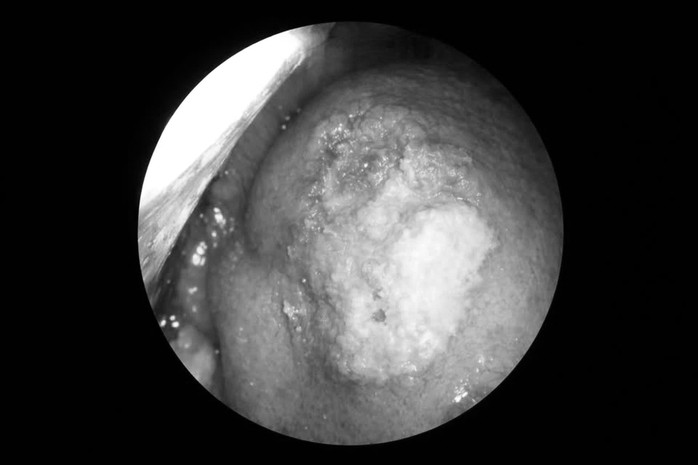

Tổn thương vùng lưỡi của bệnh nhân ung thư lưỡi